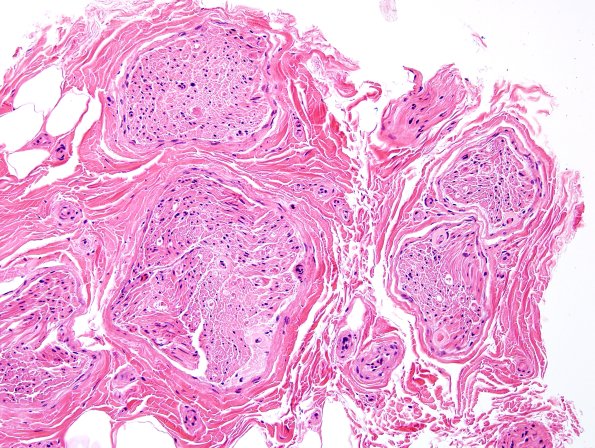

Case 5 History ---- The patient is a 44 year old woman with a clinical suspicion of amyloidosis and neuropathy. Operative procedure: Left sural nerve biopsy. ---- 5A1,2 Multiple endoneurial blood vessels show irregularly thickened walls and endoneurial matrix by pink amorphous material. There is no evidence of vasculitis or inflammation. (H&E)